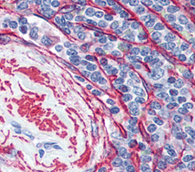

Vector Laboratories’ portfolio of immunofluorescence (IF) reagents optimize every step of the process.

With reagents that streamline antigen retrieval to preserving mounted tissue samples, their catalog supports the IF workflow from start to finish.

They also offer functionalized solutions for challenges like species-on-species detection and multiplexing so researchers can achieve exceptional sensitivity,

specificity, and reproducibility in even the most advanced IF applications.